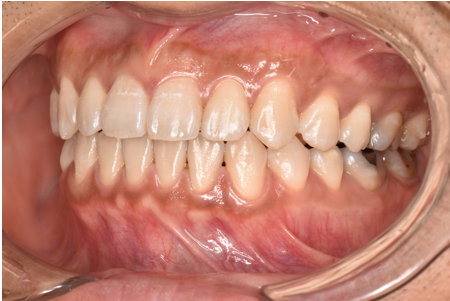

治療後

| 術後の経過・現在の様子 | 予定通りに治療が完了しました。 患者様にも「思っていたより痛みもなく、綺麗に並んで嬉しい」とご満足いただけました。 |